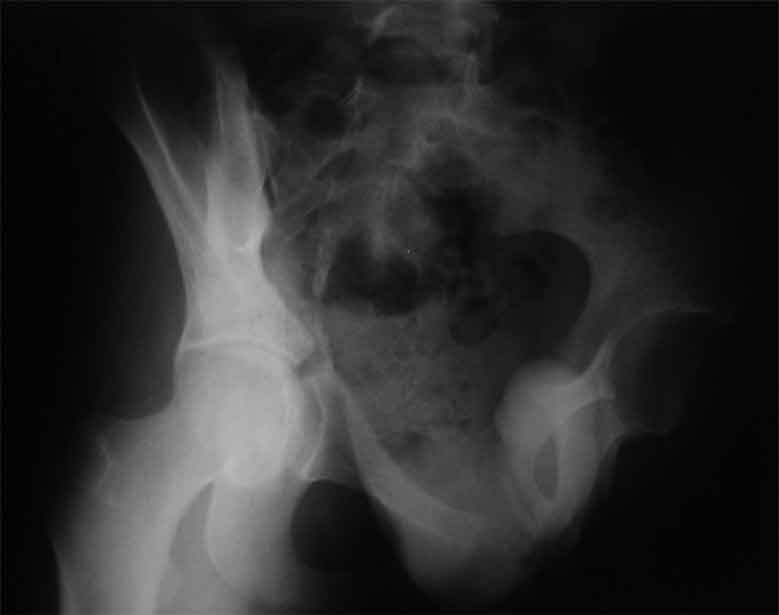

Уважаемые коллеги, сложный случай, интересует ваше мнение. Травма 2 месяца назад, в результате ДТП. При поступлении в лечебное учреждение по м/ж выполнено формирование культи на уровне в/3 левого бедра по (травматический дефект левой н/конечности), в послеоперационном периоде раневая инфекция, остеомиелит - экзартикуляция.

Повреждение таза лечилось консервативно. Интересует ваше мнение по поводу тактики лечения, попытаться свести аппаратом, а потом открытый этап (каким доступом/доступами)? другие варианты? С уважением Максим Агалаков

продолжение темы. не увидел энтузиазма в обсуждении. Вопросы прежние, первым этапом закрыто устранили вертикальное и передне-заднее смещение. Каким образом восстановить целостность тазового кольца, из каких доступов? Снимки в приложении